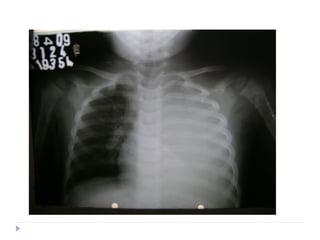

 Derrame pleural

 Pneumatoceles

 Pneumotórax /piopneumotórax

 Pneumonia necrotizante/Abscesso pulmonar

outras.

Complicações

1 2